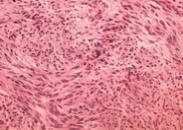

子宫内膜间质肉瘤

628健康网为您分享有关子宫内膜间质肉瘤的症状,子宫内膜间质肉瘤的治疗方法,子宫内膜间质肉瘤的预防知识,子宫内膜间质肉...